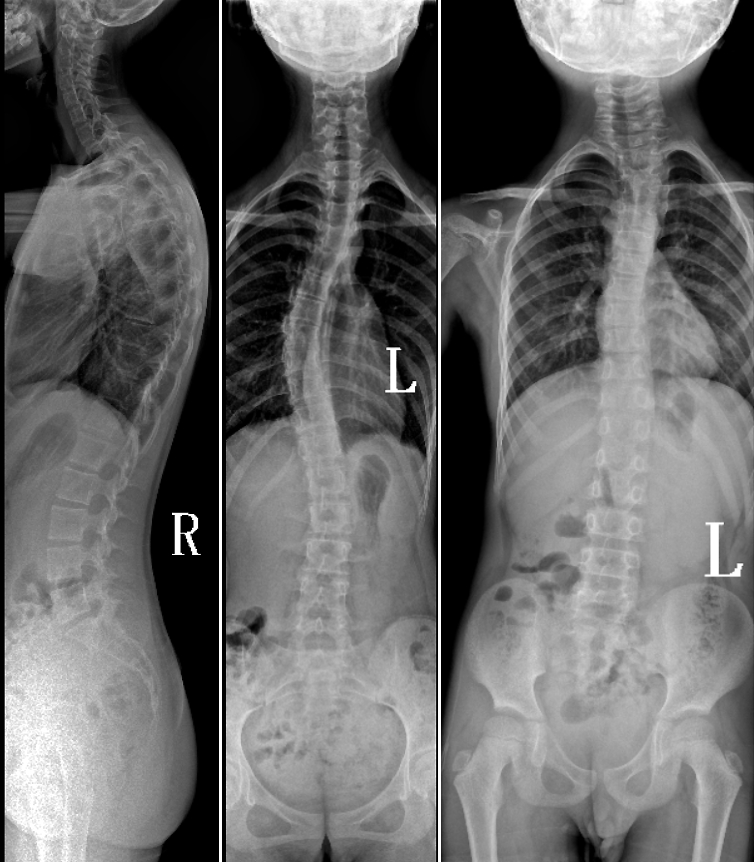

DR是臨床骨科的重要檢查手段之一。在骨科檢查中,脊柱矯形、長骨骨折、腰椎退行性病變等,需要采集脊柱、下肢全景圖像,輔助醫(yī)生臨床診斷,從而制定科學(xué)的治療方案,普愛醫(yī)療的大視野平板動態(tài)DR就像是一座橋梁,連接起現(xiàn)代醫(yī)療技術(shù)與當(dāng)?shù)厝嗣竦尼t(yī)療需求。

普愛醫(yī)療自主研發(fā)的大視野平板動態(tài),采用17"*34"的有效視野,一次曝光即可得到全脊柱或全下肢影像。相較于多張攝影再軟件拼接的DR設(shè)備,PLX8600解決了拼接圖像存在密度不均勻,拼接處圖像配準(zhǔn)和放大效應(yīng)等問題,給臨床帶來了真正的大視野影像解決方案。